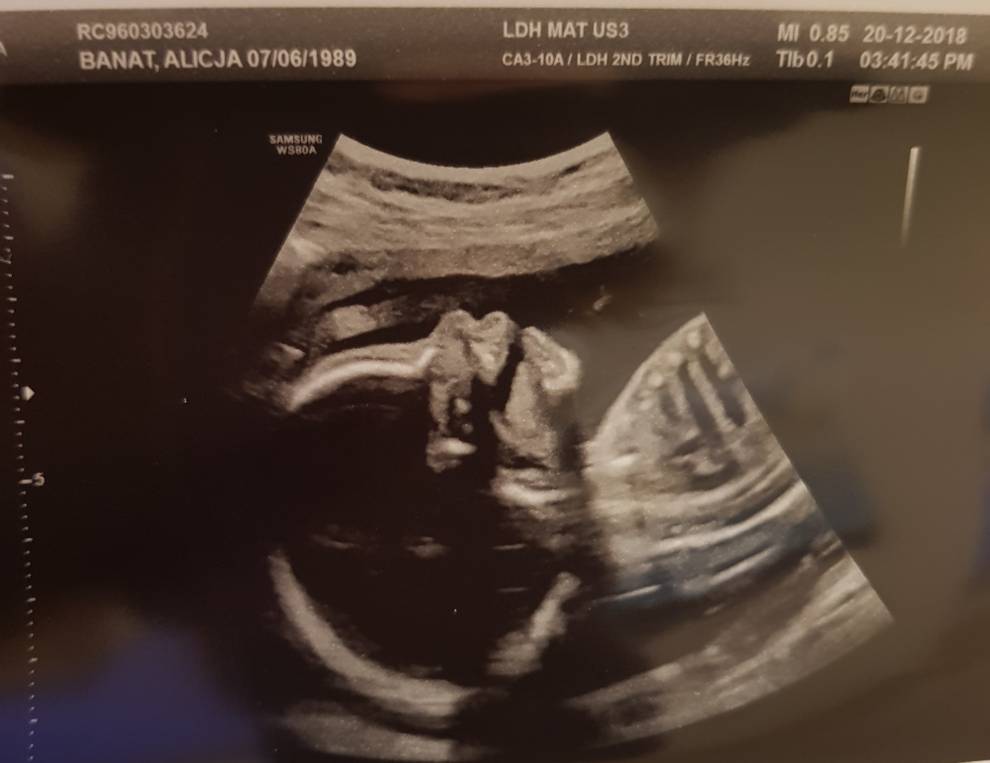

GratulacjeHej kochane. Tu kari21 ze zmienionym nickiem. Daje znac co u nas bo wczoraj powiedzialam o ciazy mamie wiec mam juz w nosie kto mnie czyta a kto nie i co myslijestesmy obecnie po 5 stratach pod rzad a 6 w sumie i w 21 tyg ciazy. Tydzien temu mielismy usg polowkowe, spodziewamy sie 3 synka, zdrowego [emoji7] z terminem w maju aczkolwiek termin cesarki bede miala wyznaczony na koniec kwietnia. Zobacz załącznik 928097